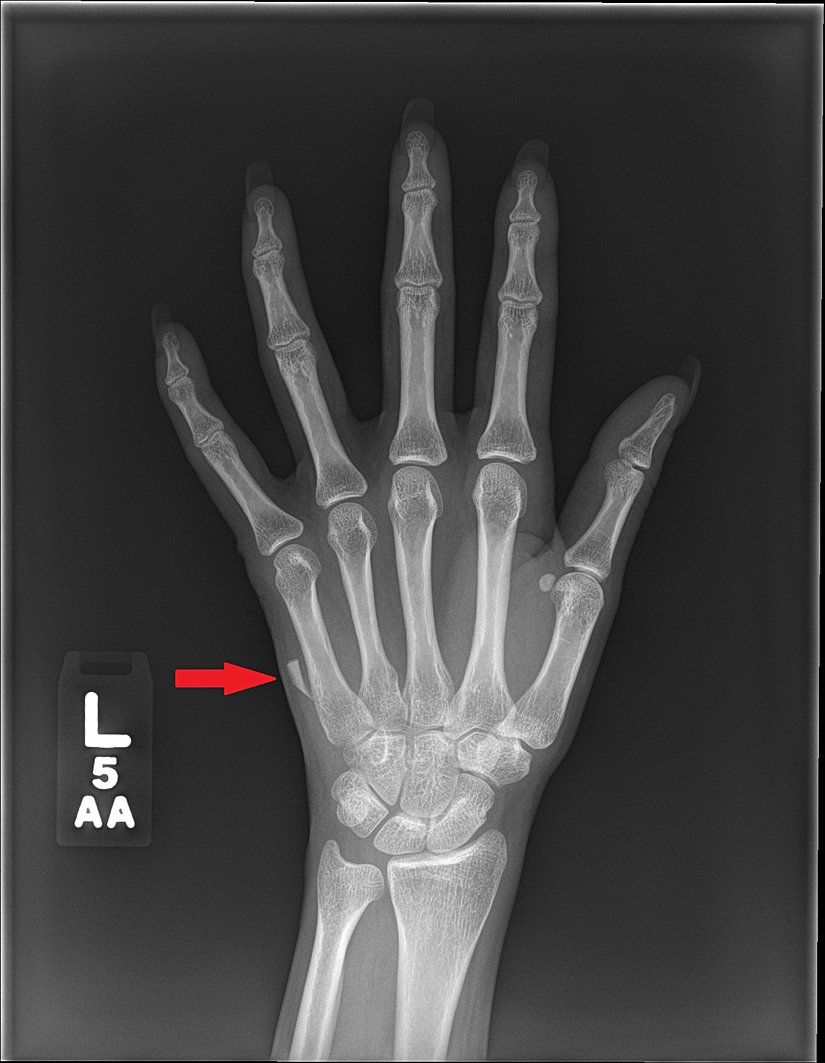

İnsan vücudunun X-ışınına verdiği tepkinin farklı olan dokularının görüntülenmesi hem tanı hem de tedavi için her zaman son derece önemli bulunmuştur. Öyle ki, görüntüleme eşliğinde tedavinin gerçekleştirilmesi, birçok branş için altın standart halindedir. Örneğin; kemik dokusu X-ışını ile çalışan görüntüleme yöntemlerinde izlenmesi kolay ve başarılı bulunurken, yumuşak doku maalesef yetersiz görüntülenmektedir. X-ışınını geçiren dokular radyolusent/hipodens olarak izlenirken; X-ışınını absorbe eden dokular radyoopak/hiperdens olarak görülmektedir. Sert dokuların radyoopak olarak izlenmesi, bunlara ait patolojilerin tanı ve tedavilerinde önemli bir role sahiptir.

Ne var ki sert dokuya ait başlangıç lezyonlarının X-ışını ile görüntü vermesi çoğu zaman mümkün değildir ve klinisyenin fark etmesi mümkün olmayabilir. Elde edilen görüntü, alışık olduğumuz "gri tonlarında" izlenirken, patolojinin verdiği gri tonunun ayırt edilmesi görüntüleme cihazına, görüntünün incelendiği ekranın kalitesine, inceleyen hekimin ton ayırıcılığına ve göz yorgunluğuna, ortamın ışıklandırılmasına bağlıdır. Bu faktörlerin büyük kısmı mühendislik çalışmalarına bağımlıdır ve görüntüleme yöntemlerinin kalitesinin artması tanı ve tedavi planlamasını kolaylaştırır.[1]